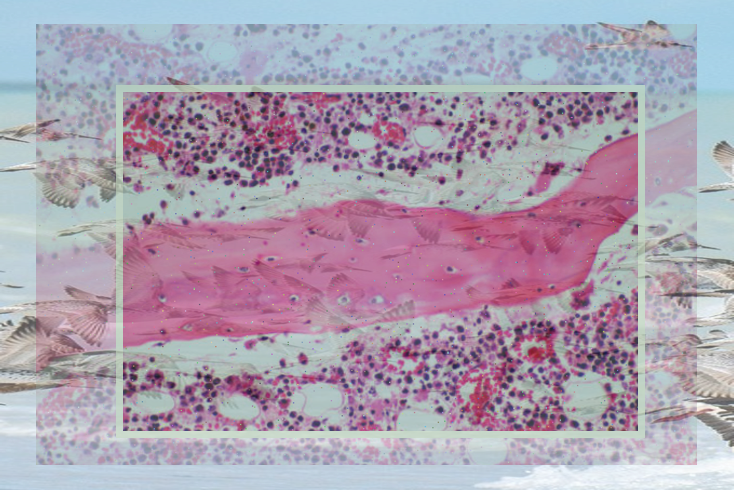

자궁경부 편평상피세포암종 진단과 치료

자궁경부 편평상피세포암종 진단과 치료 자궁경부 편평상피세포암종은 여성들 사이에서 흔히 발생하는 암 ...